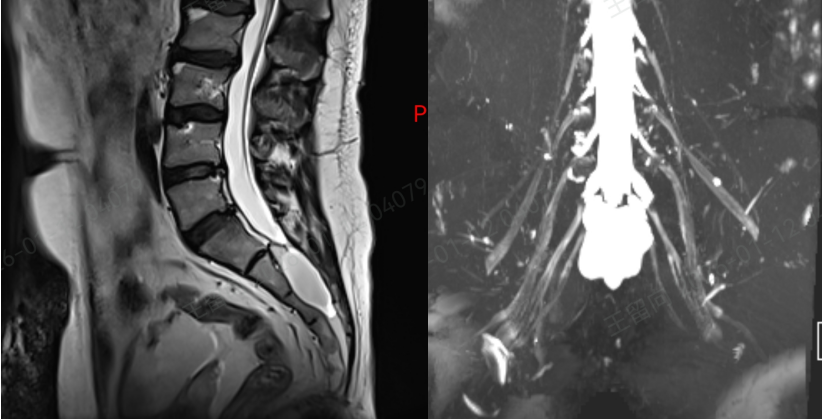

接诊后,孙红山副主任医师团队立即为刘先生展开全面评估,结合详细问诊和复查的核磁共振(MRI)结果,明确诊断其疼痛的根源正是骶管囊肿。

骶管囊肿发生在脊柱尾端的骶管内,由于先天发育缺陷或后天创伤等原因,骶管内部结构变得薄弱,直立状态下,脑脊液会遵循 “水往低处流” 的原则,单向流入神经根袖,长期下来导致神经根袖膨胀,形成充满脑脊液的水囊样肿物。

作为诊断和鉴别骶管囊肿的 “金标准”,MRI 虽能清晰显示病灶,但由于大众对这种疾病普遍缺乏正确认识,临床中误诊漏诊情况时有发生。

而刘先生的疼痛,正是因为囊肿内的神经根被牵拉,同时邻近神经根受到挤压,才导致了持续性的腰骶部疼痛,并非简单的腰肌劳损。